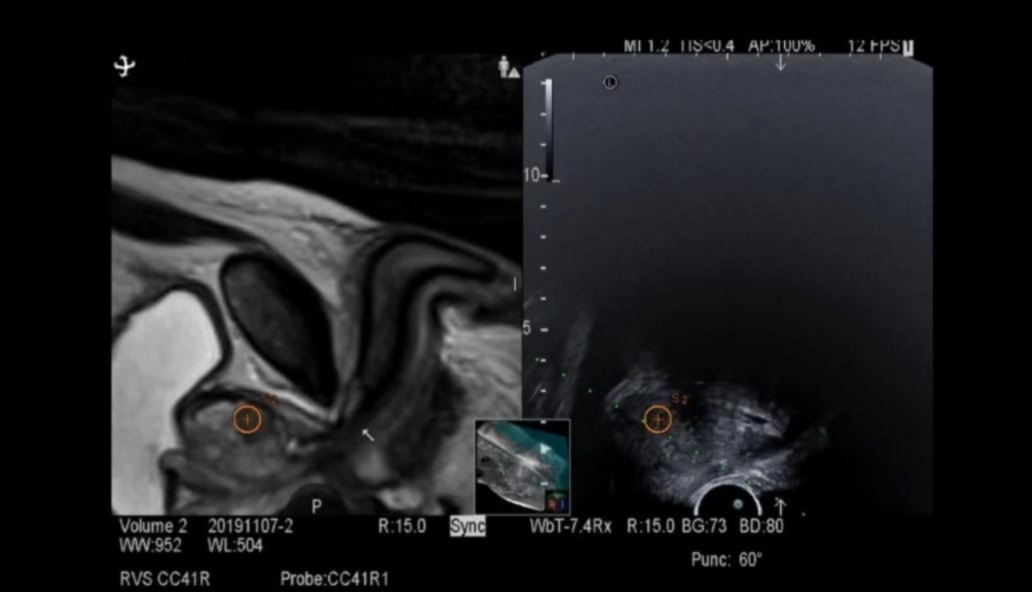

Az új technika a multiparametrikus MRI-vizsgálat képeit ötvözi a valós idejű, transzrektális ultrahangvezetéssel. A speciális szoftver a két képanyagot egy háromdimenziós, rendkívül részletes térképpé alakítja, így az orvosok pontosan tudják meghatározni, mely prosztataterületekről szükséges mintát venni. Ez jelentős előrelépés a korábbi, úgynevezett „vakon” végzett biopsziákhoz képest, hiszen a célzott szövettani mintavétel lényegesen növeli a diagnózis megbízhatóságát.

A beavatkozást a kórház Fujifilm Arietta 880 típusú ultrahangkészülékével végzik, általános intravénás altatásban, egynapos kórházi ellátás keretében. A páciens általában gyorsan felépül, a vizsgálatra pedig háziorvosi beutaló és előzetes urológiai konzultáció alapján lehet jelentkezni.

A módszer fontos előnye, hogy a PIRADS-pontszám alapján korábban gyanúsnak ítélt elváltozásokat célzottan lehet vizsgálni. Ennek köszönhetően az orvosi csapat sokkal pontosabban tudja meghatározni a további kezelési irányt – legyen szó aktív megfigyelésről, fókuszált beavatkozásról vagy akár radikális terápiáról. A technológia egyszerre biztosít nagy precizitást, biztonságot és kényelmet, ezzel erősítve a korszerű képalkotó diagnosztika szerepét a korai felismerésben.